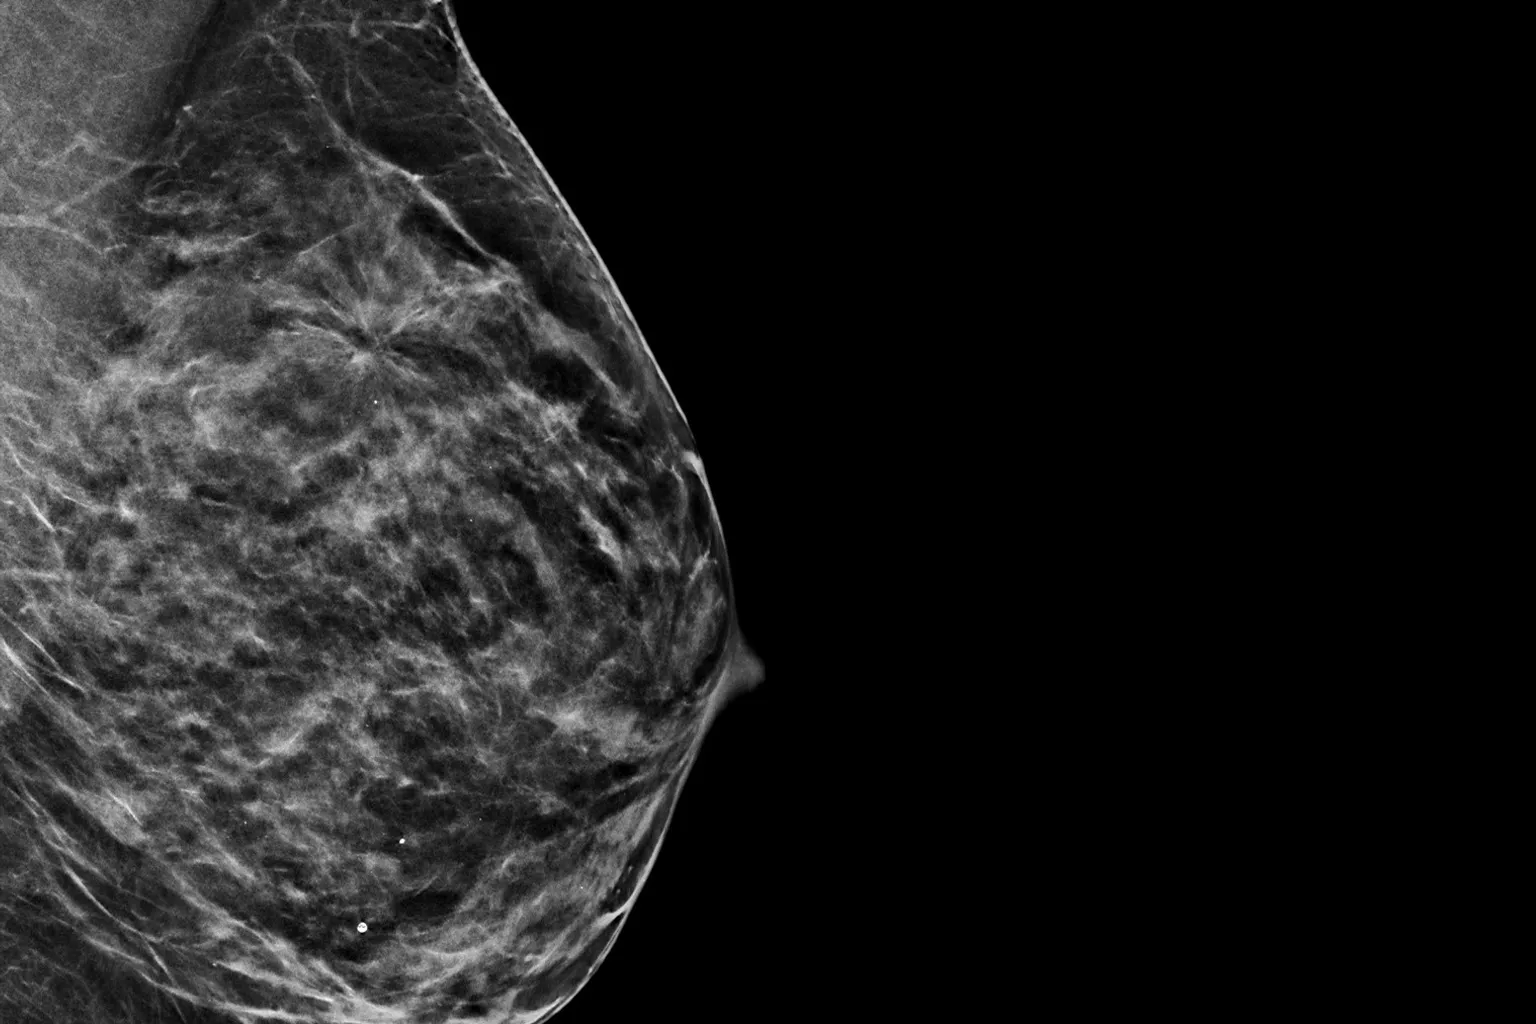

Raise your breast cancer screening performance1-4 with C-View software and instantly generated synthesized 2D images. It not only enhances details and speeds up the analysis, but also reduces radiation dose levels for your patients. C-View 2D images are clinically proven3,5 and FDA approved to diagnostically replace the FFDM images within a tomosynthesis screening exam.

Architectural distortions, mass lesions, and bright spots commonly found in microcalcifications are more visible in the C-View 2D image than on the traditional FFDM 2D images or tomo slices.4,6-9

Architectural distortions, mass lesions, and bright spots commonly found in microcalcifications, are more visible in the C-View 2D image than on the traditional FFDM 2D image or tomo slice.4,6-9